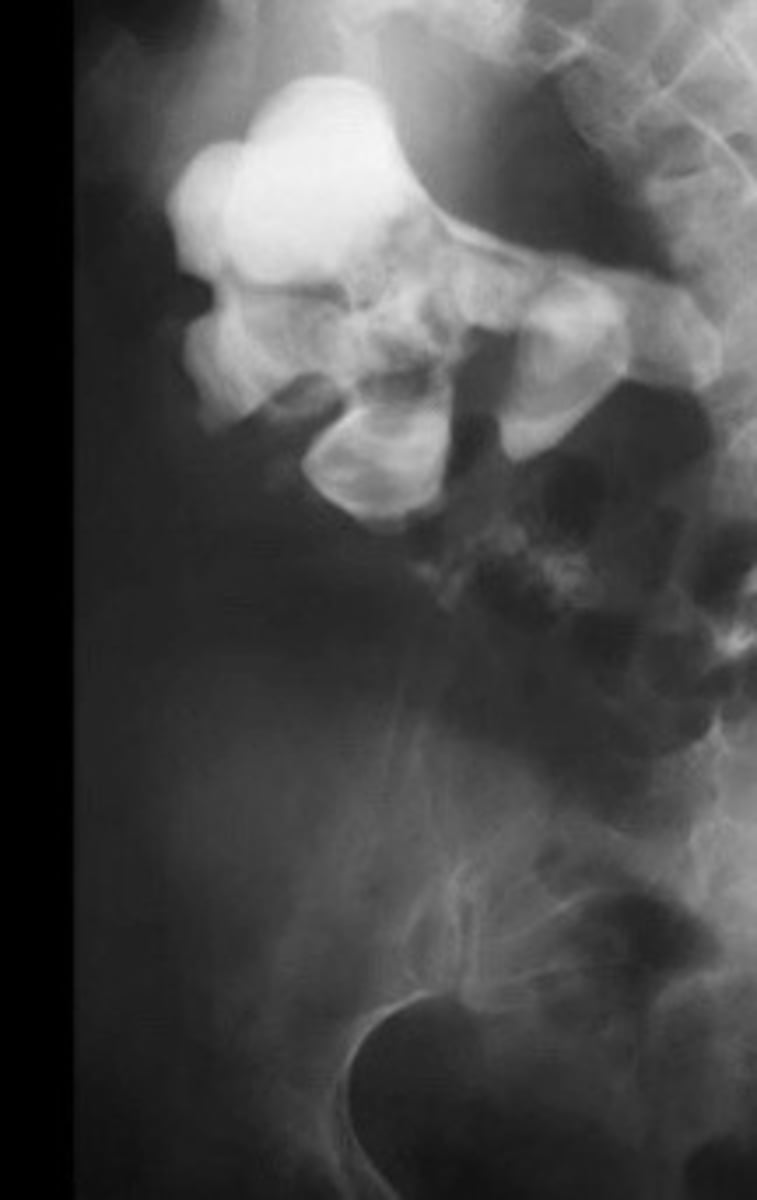

Staghorn calculi

What does this image show

Calcifications filling all or most of the renal collection system/calyces

What is staghorn calculi

X-ray of staghorn calculi